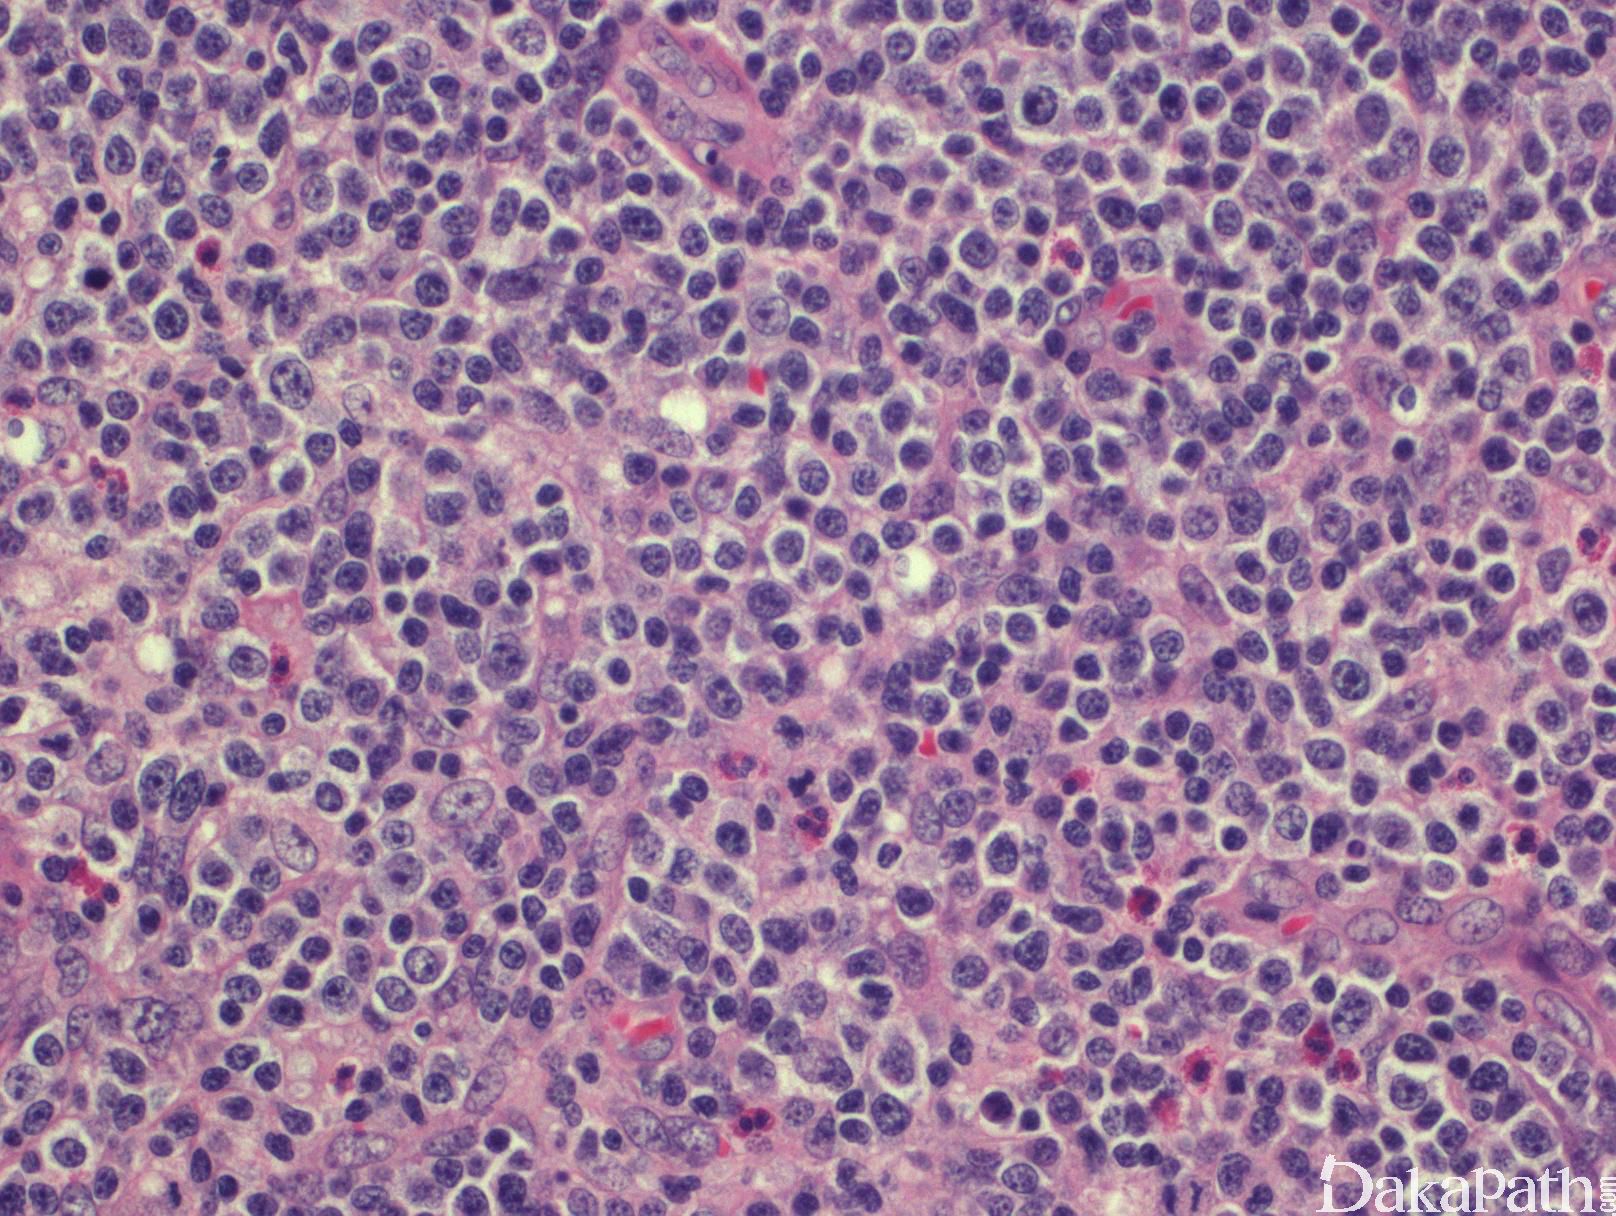

- 淋巴结正常结构消失,代之以弥漫肿瘤增生,有时增生以副皮质区为主。背景血管增多,主要是高内皮小静脉,分枝丰富。皮肤常侵犯真皮和皮下,呈弥漫侵润或形成结节。骨髓为间质弥漫或局灶浸润。

- 肿瘤细胞小到中等,但也可以是大细胞,以病例而定。多数为中等大小,胞核不规则,核仁易见,核分裂频繁,胞质少到中等,有的表现为透亮胞质。有时可见 HRS 样细胞。背景通常混有很多反应性小淋巴细胞、嗜酸性细胞、组织细胞和浆细胞。